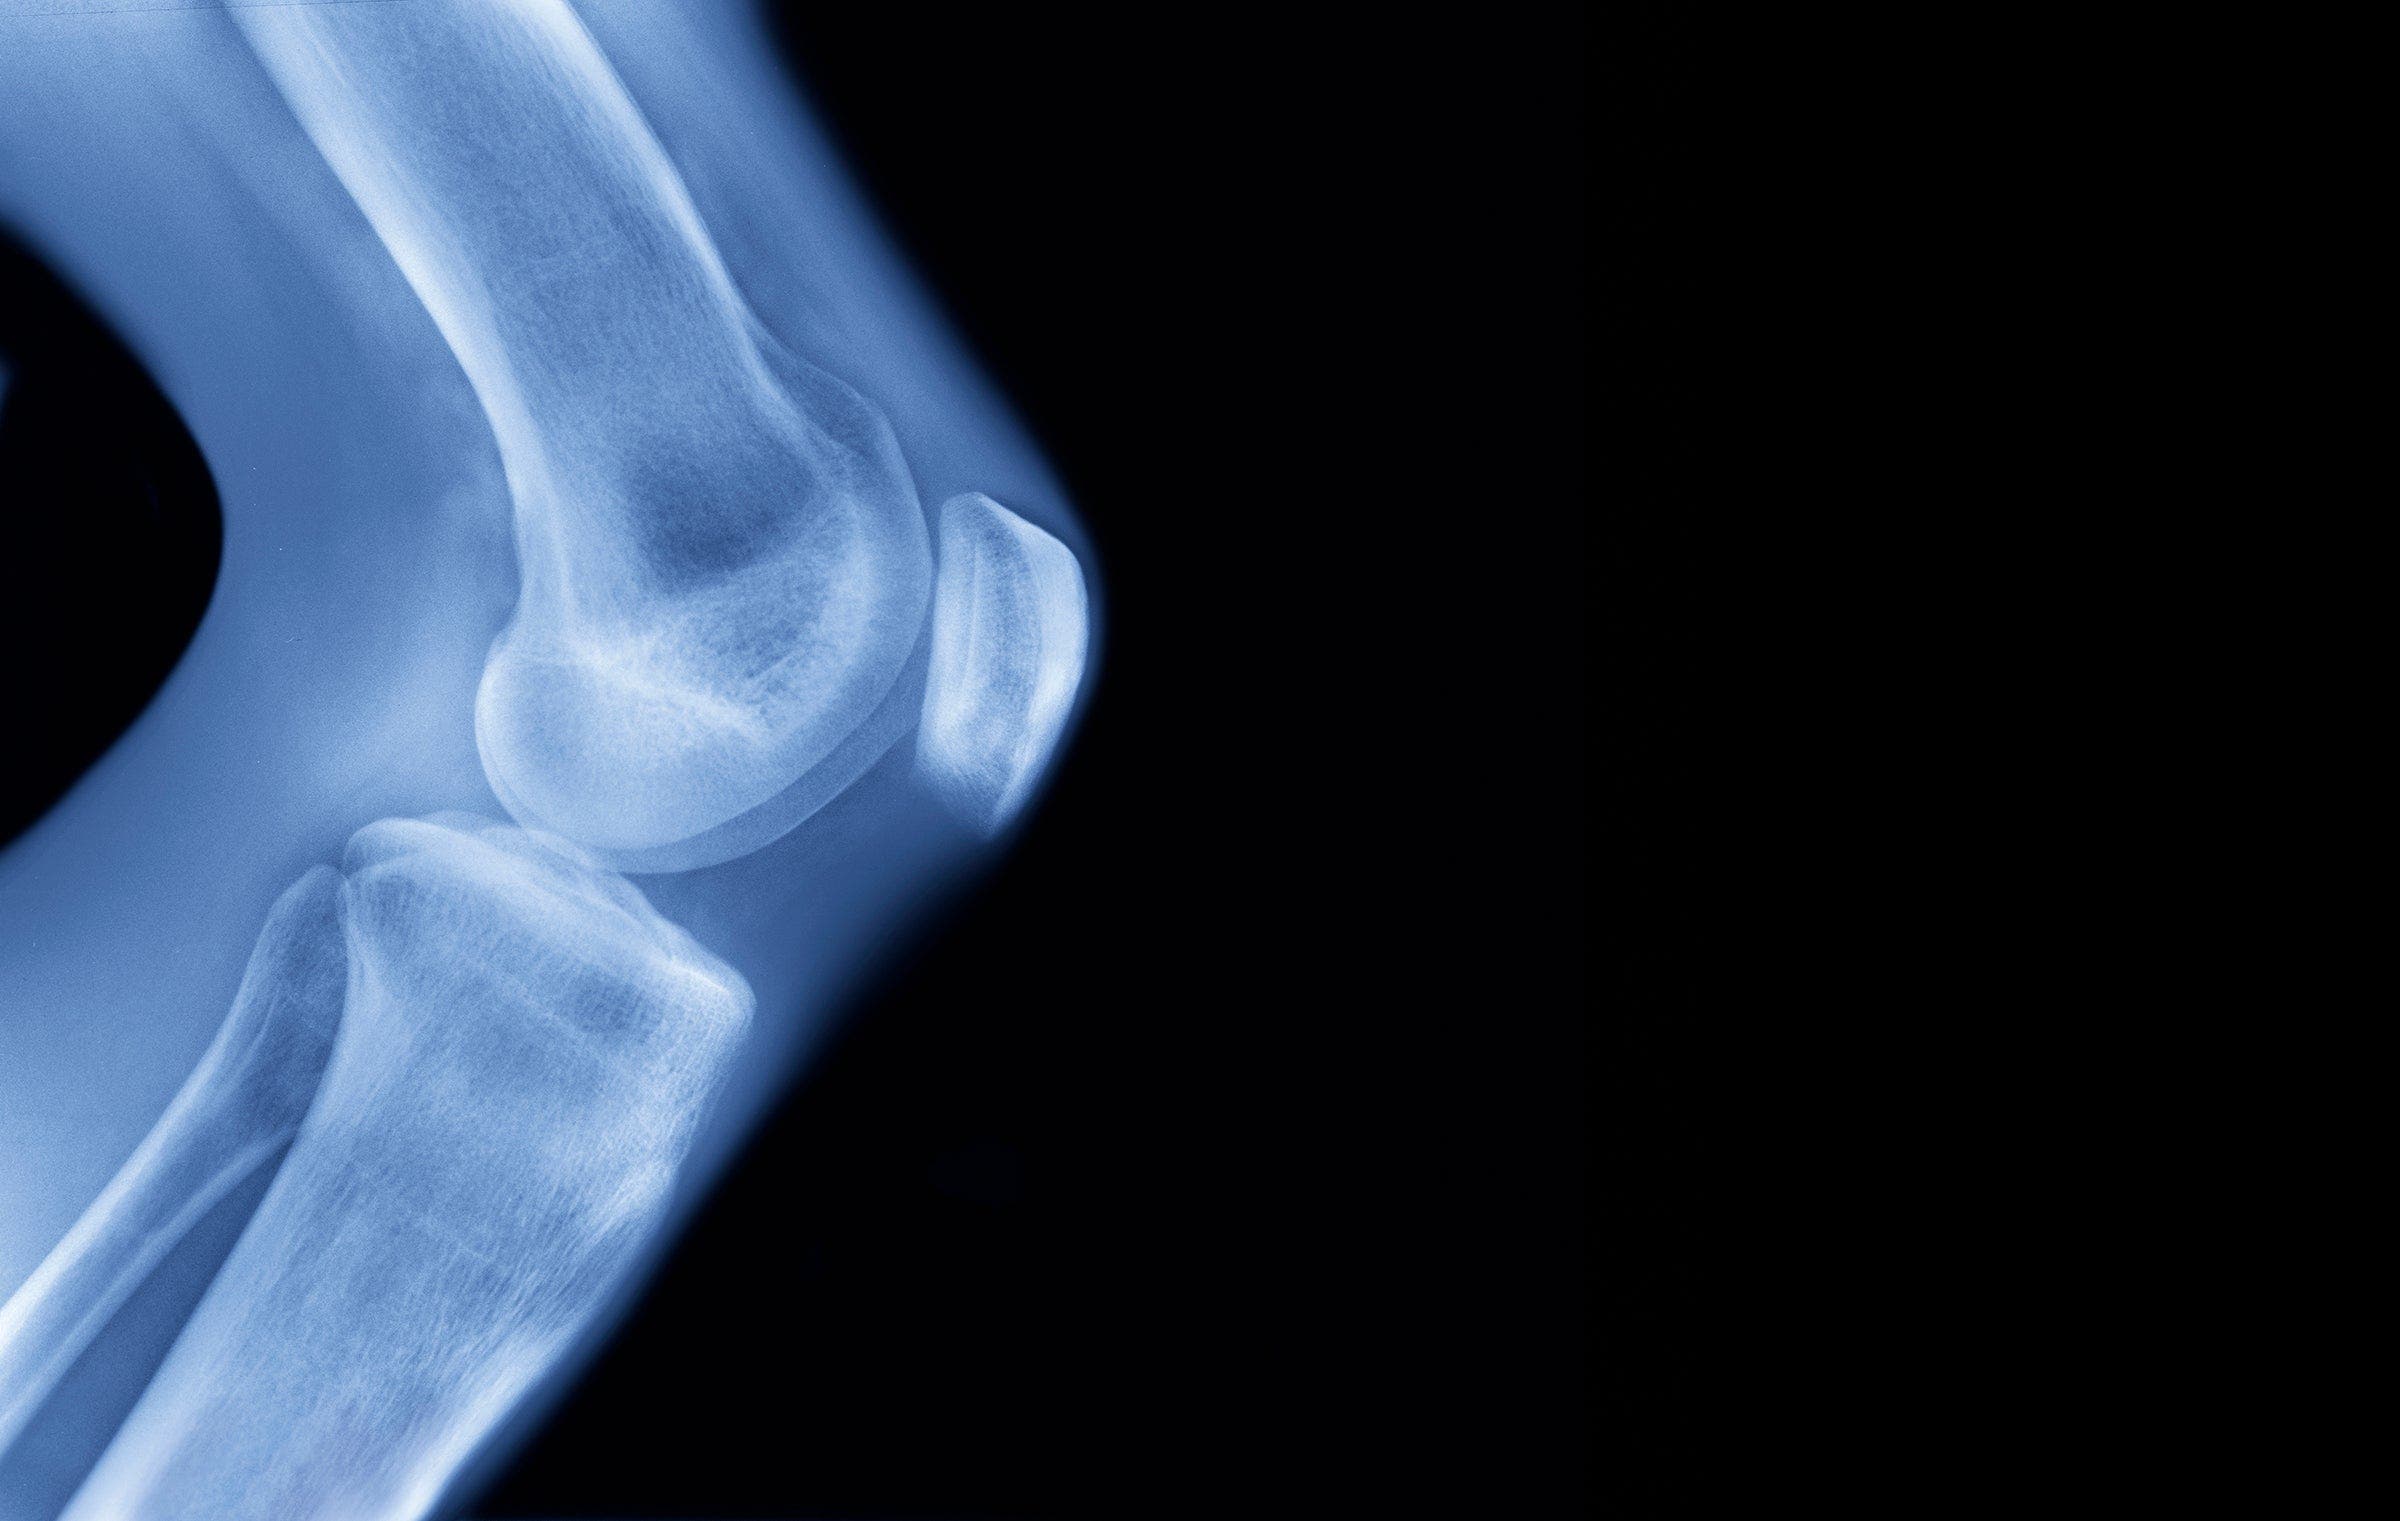

(Photo: Getty Images)

In a Sept. 3 paper in Sports Medicine, Esculier’s team examined 43 studies that had used MRI to measure the effect of running on cartilage.

One major finding of these studies, he says, was that the impact from running squeezes water out of cartilage and into the underlying bone. That means that an MRI taken immediately after running will show a decrease in cartilage thickness.

Meanwhile, his preliminary work has examined women runners in their mid-fifties, some with arthritic knees and some without, using MRI to see how their cartilage reacts and recovers. The main finding so far Esculier says, is that you need to listen to your body. If it hurts, adjust your recovery time accordingly.